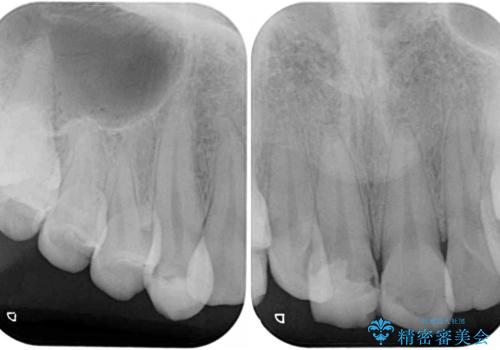

- 転倒により前歯の一部が欠けてしまったとのことで来院された患者様です。

神経が保存できる歯、神経を除去しなければならない歯、抜歯が必要な歯があり、ブリッジやインプラントなどによる治療を提案しました。

本来であれば積極的に小臼歯を抜歯して口元を下げても良いのですが、前歯を1本抜歯しないといけなくなったため、非抜歯矯正をインビザラインを用いて行うこととしました。

補助装置により上顎歯列を遠心移動させたため、非抜歯でしたが口元の突出感をある程度改善させることができました。

欠けてしまった前歯もオールセラミッククラウンにて自然に補綴することができました。